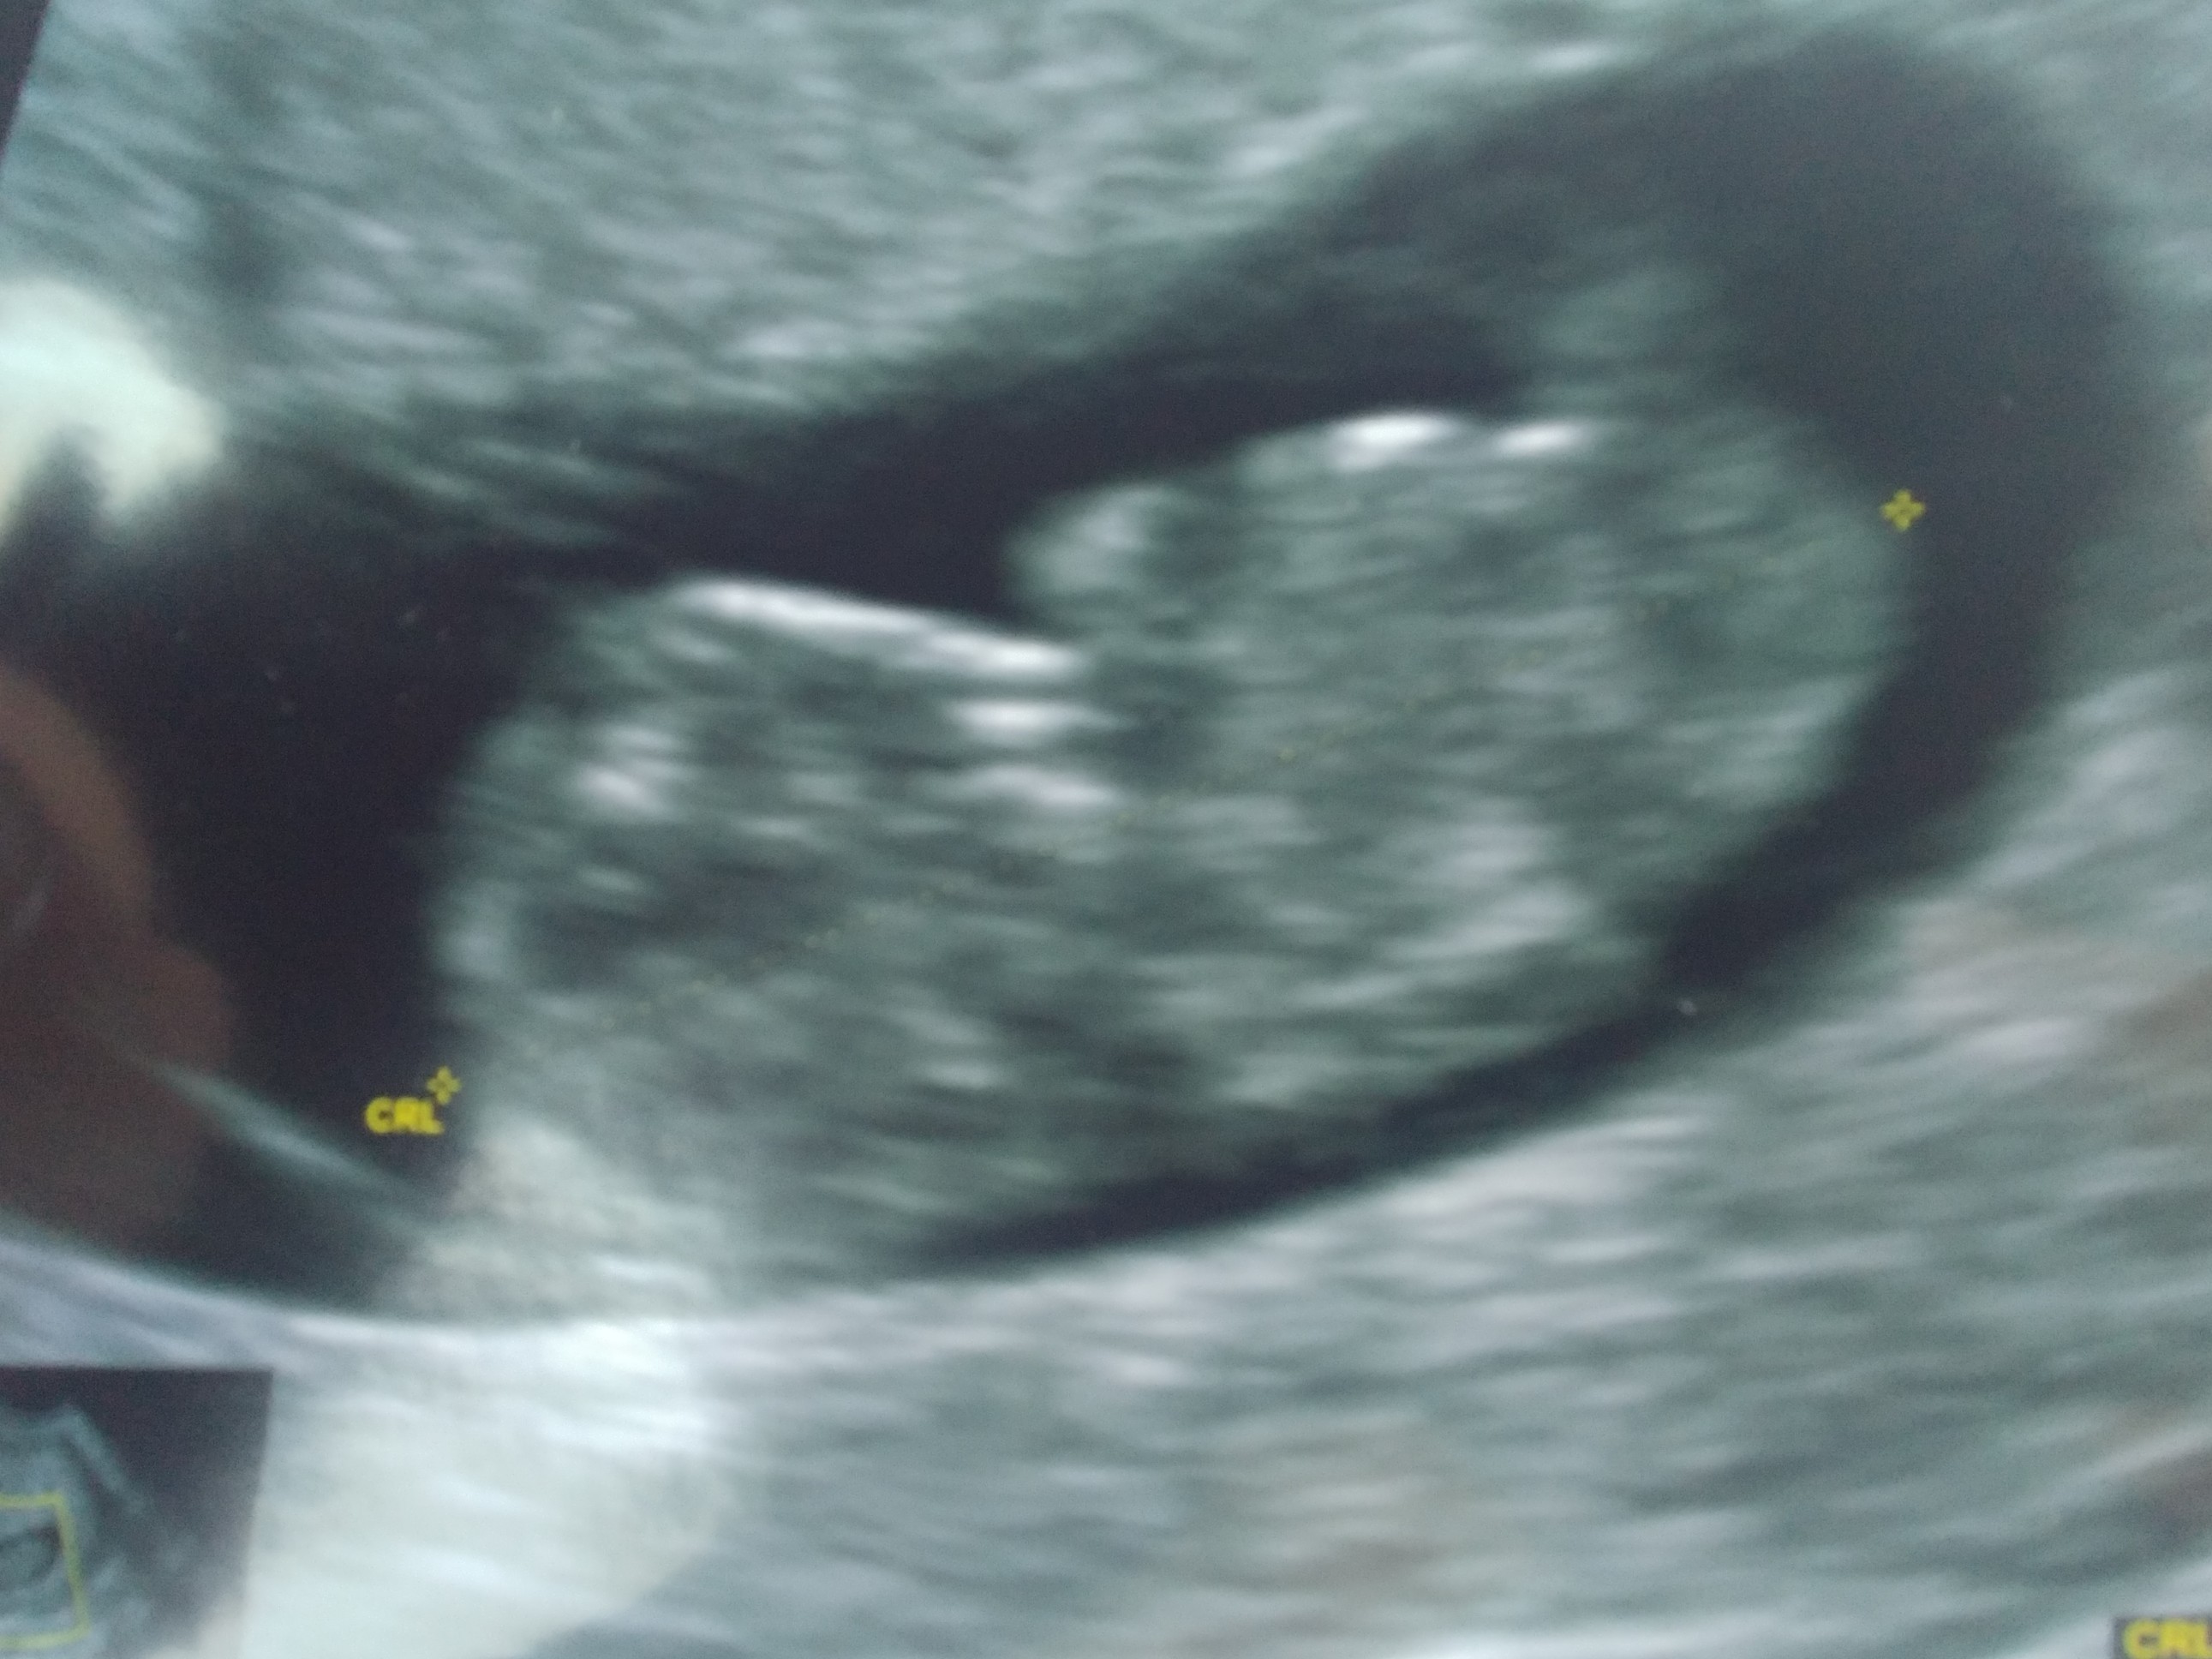

Boże, to straszneSerduszko już nie bije. Dostalam skierowanie do szpitala. Jedziemy teraz na izbę przyjęć sprawdzić na innym usg bo tak mi lekarz kazał. Lekarz, który mnie badał pracuje w szpitalu więc dzwonił, że przyjedziemy teraz sprawdzić.